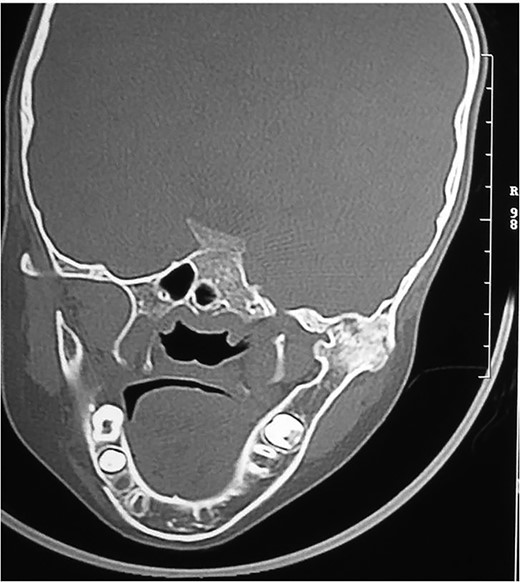

RADIOGRAPHIC FEATURES

Orthopantomogram and computed tomography (CT) scan with 3D reconstruction revealed a lack of structural organization and obliteration of right TMJ space. The right body of mandible was arch shaped due to restriction of the right condyle with right coronoid pushing upwards. There was also occlusal cant on frontal CT scan. Coronal view of CT scan demonstrated ankylotic mass. Based on these finding, a diagnosis of unilateral bony ankylosis of TMJ on right side was confirmed (Fig. 3).